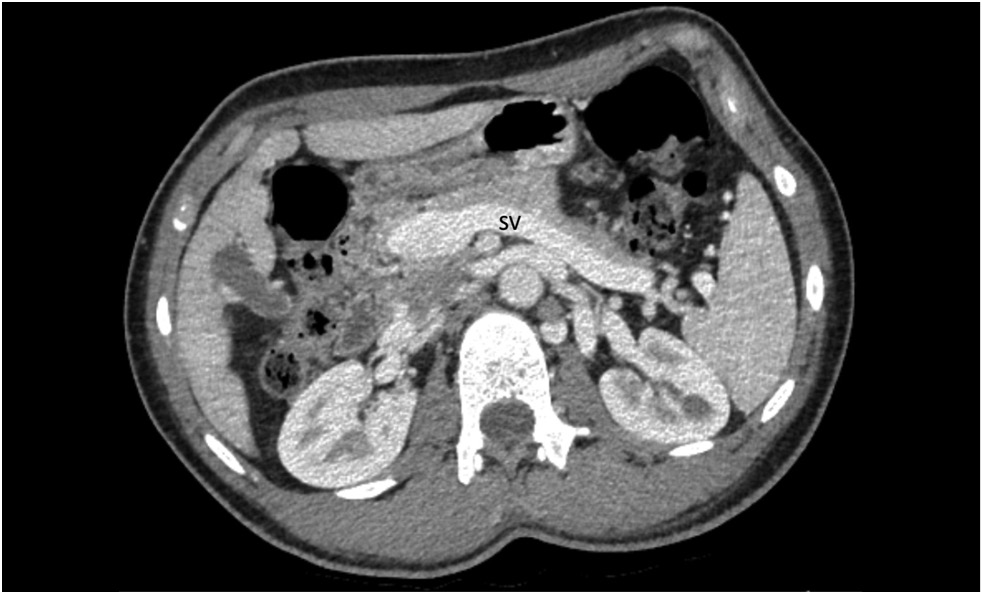

本文描述了一个15岁患者的Ib型Abernethy畸形的临床病例,该患者长期有高血压、反复鼻出血、胸痛、头晕、呼吸困难、运动耐力低下、便血、上腹痛、恶心和瘙痒等病史。经过全面检查,患者被诊断为门静脉系统异常:门静脉导管扩张,直接流入下腔静脉。还发现了肝实质中的多个结节、扩张的心腔、心肌肥厚和肺动脉高压。鉴于症状的严重性以及分流的大小和类型,一个多学科科联合会诊建议进行肝移植。

我们在本文中讨论了门静脉系统异常的诊断算法和其他可能的治疗方案。